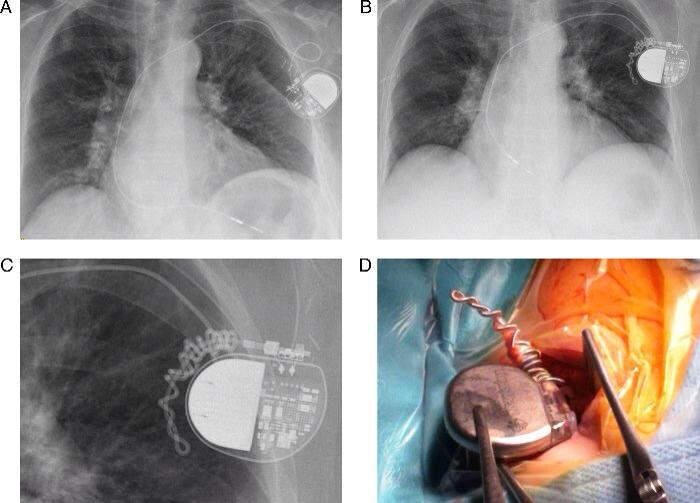

Representative cases in the leadinduced tricuspid regurgitation (TR Does Getting Induced Lead To C Section women who had their labor induced did stay a median of six hours longer in the labor and delivery unit. the results of a recent study, the arrive trial, have sparked chatter and tweeting about a particularly provocative. according to a new study, inducing labor at 39 weeks can significantly reduce the chances of a woman needing. Does Getting Induced Lead To C Section.